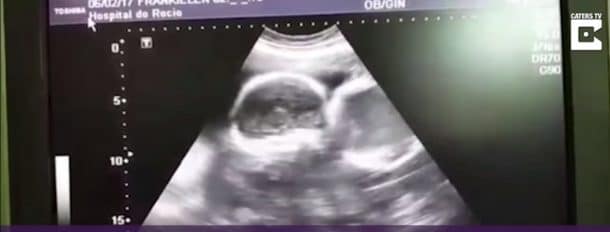

Frankelien da Silva Zampoli Padilha n’avait que 21 ans lorsqu’elle a fait une attaque cérébrale. Non seulement sa famille venait de la perdre, mais en plus elle était enceinte de plus de 9 semaines au moment de l’accident. Alors qu’il était clair que la jeune femme n’avait aucune chance de vivre, tout le monde a également immédiatement pensé à la perte des jumeaux qu’elle avait dans son ventre. Mais les médecins de l’hôpital Nosso Senhora do Rocia à Campo Largo, au sud-est du Brésil, ont remarqué que malgré le décès de la maman, les cœurs des jumeaux battaient toujours. Il a donc été décidé de placer la mère sous respiration artificielle pour que ses organes puissent continuer à développer les bébés.

Le directeur du département de neurologie, le docteur Dalton Rivabem a expliqué : « Les organes de Frankelien étaient tous intacts et fonctionnaient parfaitement, comme si elle était toujours en vie. On a pris la décision de sauver ses enfants. Et de jour en jour, on a pu observer leur croissance. » Le corps médical s’est tellement attaché à ce cas, qu’ils sont devenus très protecteurs envers la petite famille. Le papa et ses jumeaux ont droit à des visites particulières et les infirmières venaient parler aux fœtus pour les habituer à une présence féminine alors qu’ils étaient encore dans le ventre.

Il s’agit d’un record médical, car tenir une personne sous respirateur artificielle pendant 123 jours, alors qu’elle était déclarée en mort cérébrale, est une première. L’accouchement a eu lieu par césarienne, au moment où les machines de la maman ont été arrêtées, les petits son nés prématurés à presque sept mois. Les reins et le cœur de Frankelien ont été donnés à deux personnes en attente de greffe.